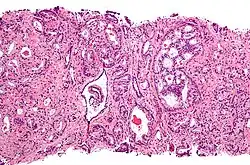

Cytological differences between normal prostate and neoplastic glands are evident in changes to the typical two cell layers of the gland. In prostatic adenocarcinoma, the basal (bottom, usually cuboidal type) cell layer is lost, with only the top layer (usually columnar to pseudostratified) remaining.

Gleason 3

Gleason 3 is a clearly infiltrative neoplasm, with extension into adjacent healthy prostate tissue. The glands alternate in size and shape, and are often long/angular. They are usually small/micro-glandular in comparison to Gleason 1 or 2 grades. However, some may be medium to large in size. The small glands of Gleason 3, in comparison to the small and poorly defined glands of pattern 4, are distinct glandular units. Mentally you could draw a circle around each of the glandular units in Gleason 3.[4][7]

Gleason 4

Gleason pattern 4 glands are no longer single/separated glands like those seen in patterns 1–3. They look fused together, difficult to distinguish, with rare lumen formation vs Gleason 1–3 which usually all have open lumens (spaces) within the glands, or can be cribriform-(resembling the cribriform plate/similar to a sieve: an item with many perforations). Fused glands are chains, nests, or groups of glands that are no longer entirely separated by stroma-(connective tissue that normally separates individual glands in this case). Fused glands contain occasional stroma giving the appearance of "partial" separation of the glands. Due to this partial separation, fused glands sometimes have a scalloped (think looking at a slice of bread with bite taken out of it) appearance at their edges.[4][7]